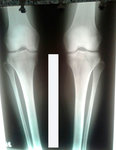

Исходник - 42 года.

Дата операции - 18.01.2017г.

РЕНТГЕН ДО ОПЕРАЦИИ